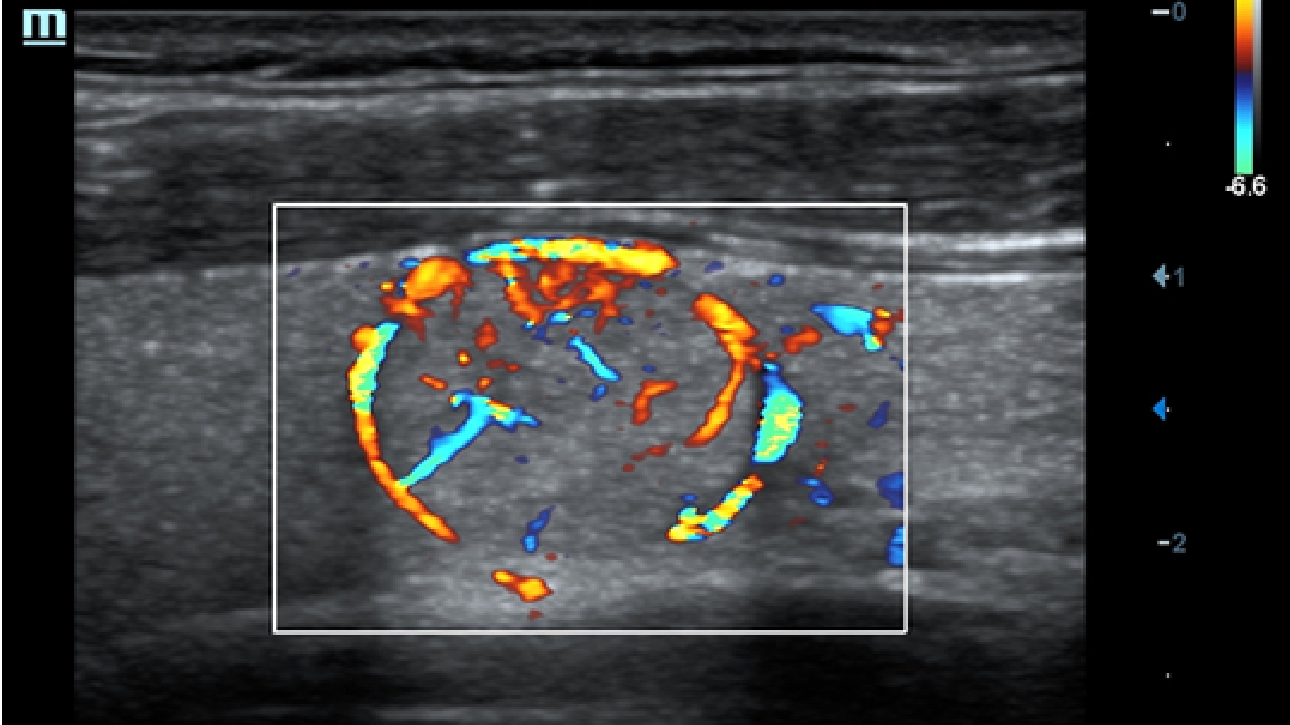

?????? ??? ???? ?? ???? ??? ??? ??? ???? ??? ??? ??? ?? ??? ???? ?????. ??? ?? ????? ???? ???? ??? ?? ??? ???? ?? ???? ??? ???? ???? ????.

???? ?? ??? ?????, X-Insight???? ??? DC-60 Exp ?? ??? ???? ???? ?? ??? ?? ??? ?? ???? ?????.